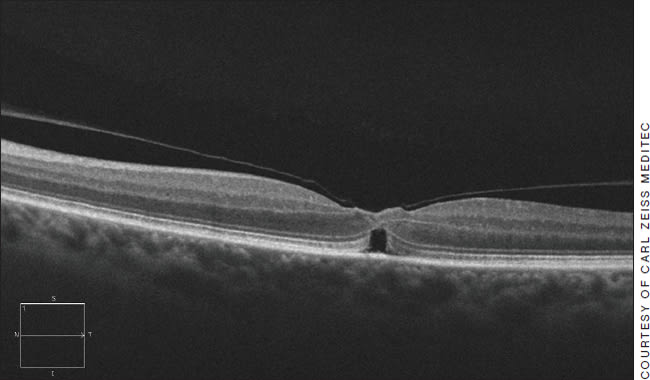

OCT evaluation can reveal macular holes (such as the one pictured) that are best referred to a retina specialist, and pseudomacular holes, which can generally be observed.

It's very rewarding when I can use OCT technology to differentiate between a macular hole and a pseudomacular hole. A fresh macular hole triggers referral to a retina specialist. The pseudomacular hole is a problem that may be carefully observed if the vision and vitreo-macular interface is stable. Additionally, when I diagnose wet AMD, the patient is referred to a retinal specialist for early intervention.